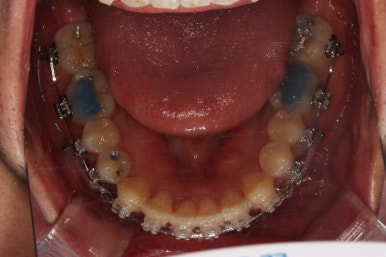

초진 시 입안의 모습입니다.

앞니가 약간 삐뚠 것 말고는 큰 문제는 없어보이네요.

장치를 부착했습니다.

이번 부산연제구교정 환자분이 선택한 장치는 엠파워 클리어라고 하는 자가결찰 세라믹 장치입니다.

최대한 빠른 시일 내에 치열을 가지런하게 해주고 미니스크류를 많이 식립하게 됩니다.